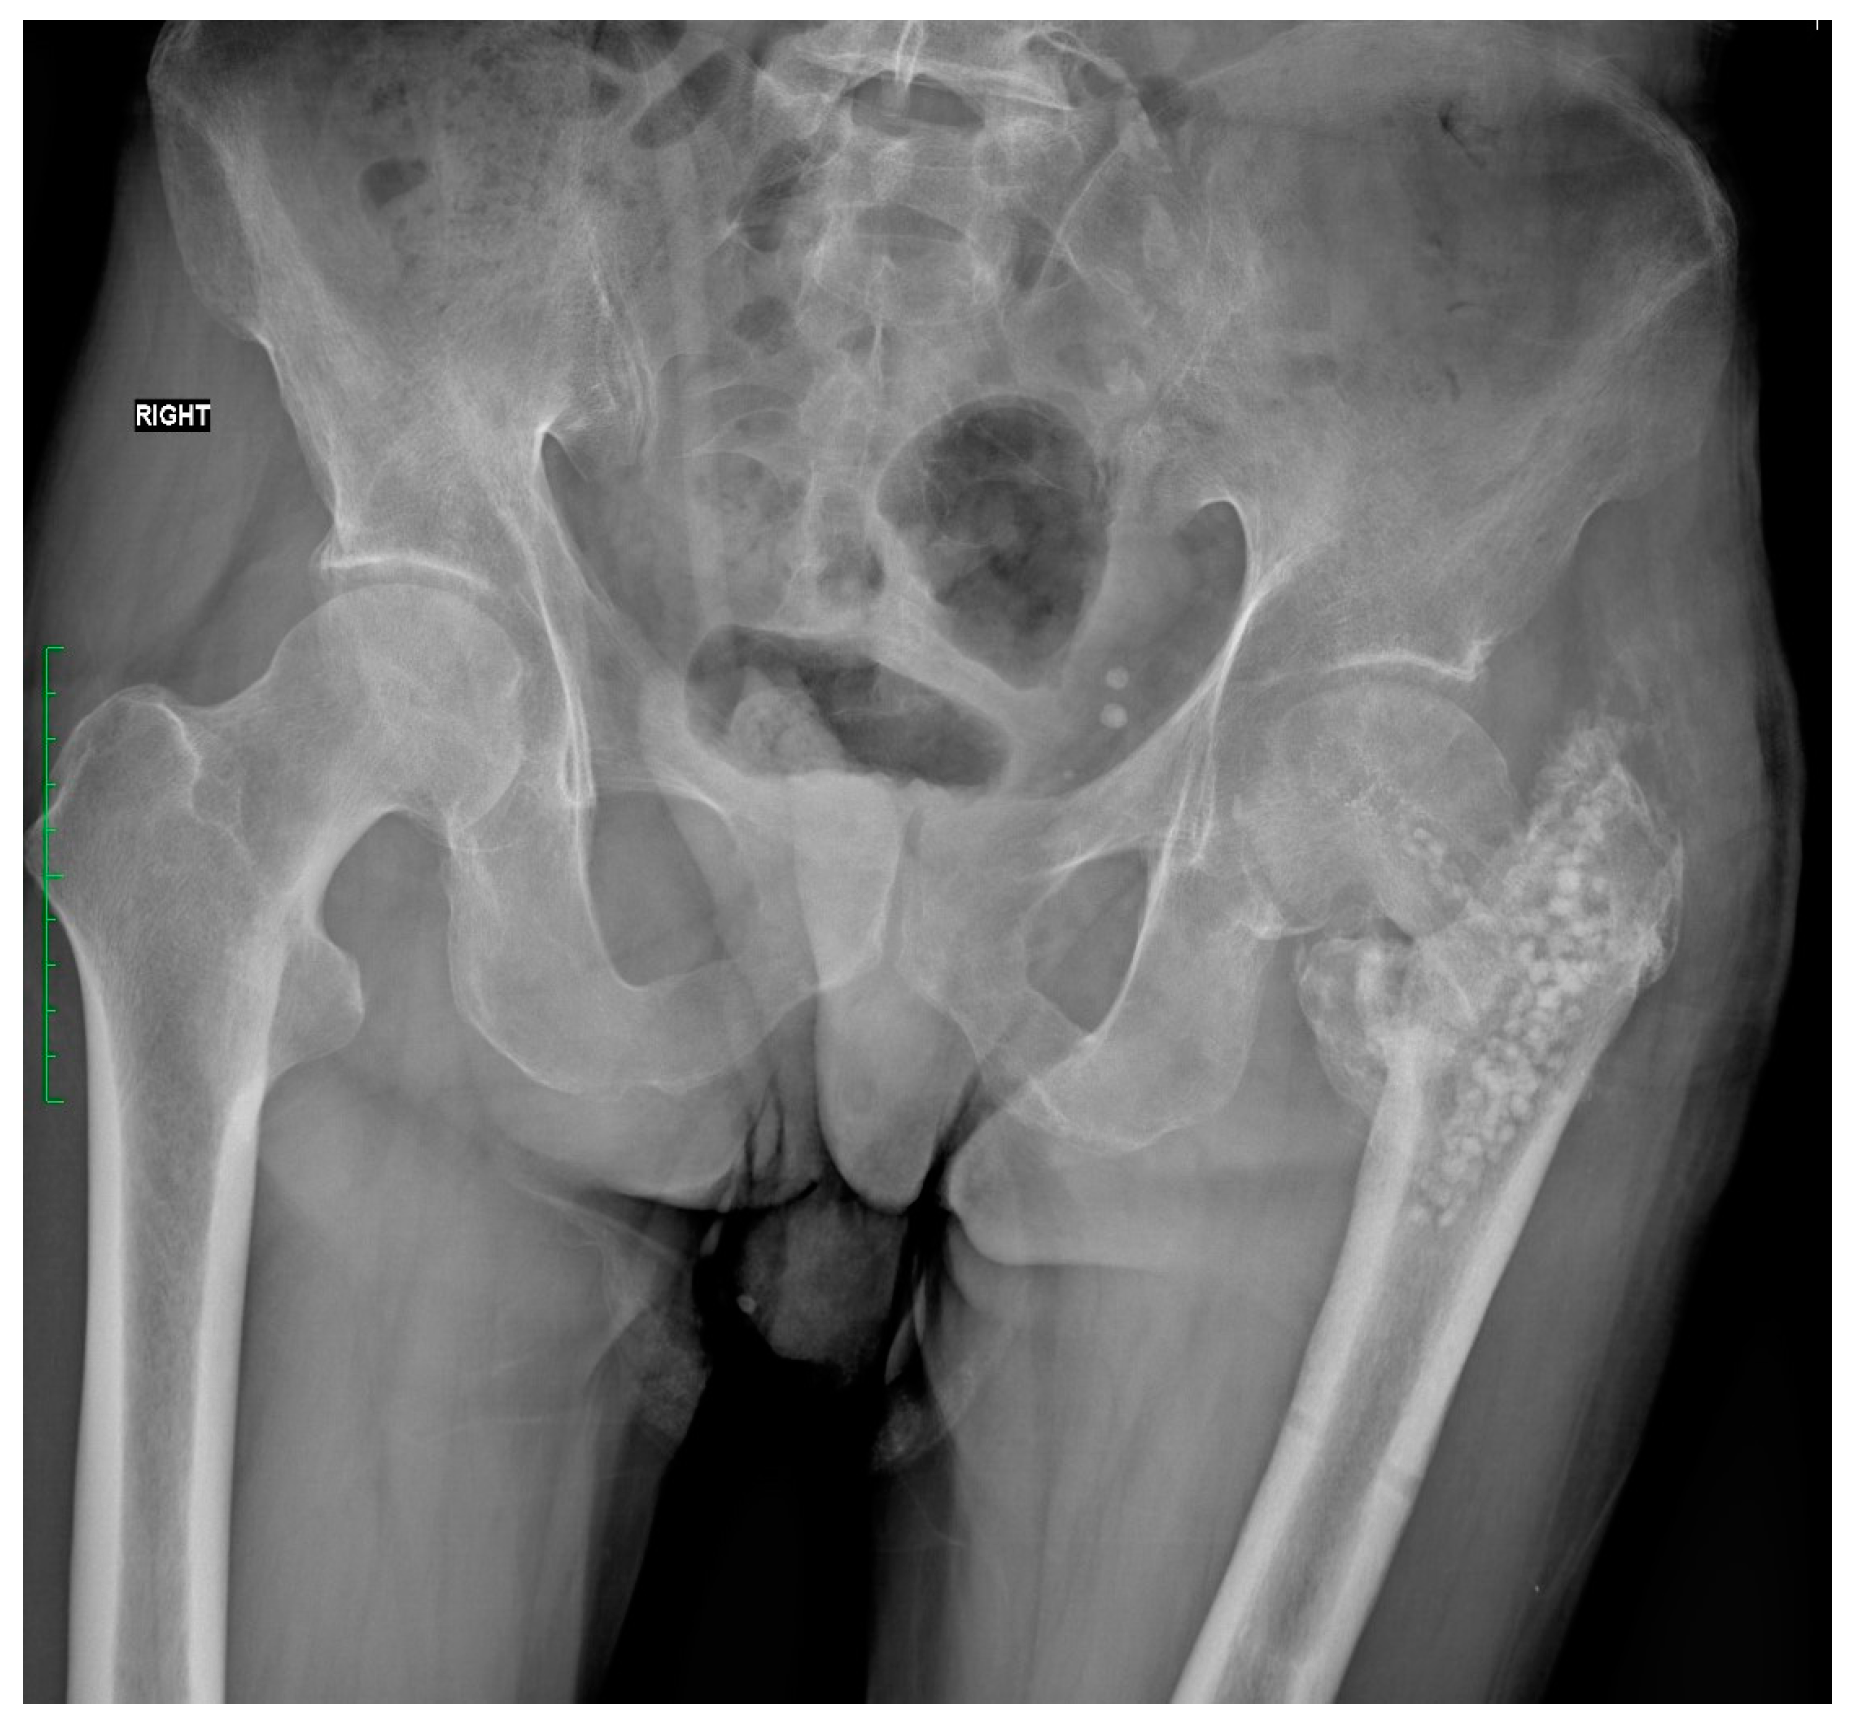

2.4. Fracture and Initial Surgery

| First Stage of Treatment—January 2023 Removal of the failed fixation, filing the bone defects with calcium sulphate antibiotic carrier | ||